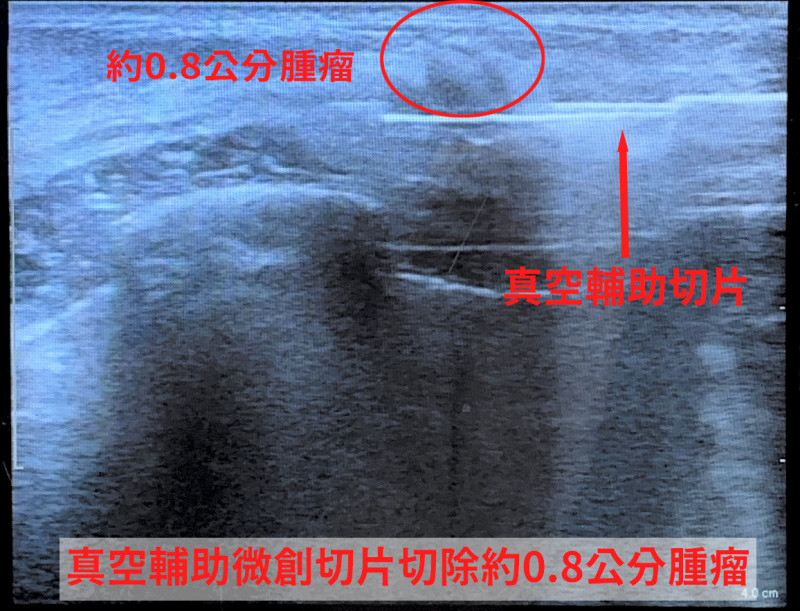

〔記者廖雪茹/新竹報導〕年僅24歲的小芬(化名)近日因乳房疼痛就醫,透過超音波檢查,發現約0.8公分不規則邊緣腫瘤,且伴隨微鈣化;雖然初次以傳統粗針切片檢查結果為良性,但影像仍顯示有異常,醫師認為癌症的風險大概10%甚至50%,醫病溝通後,進一步以「真空輔助微創切片」取得更多組織,提升診斷準確度,也可同步完整移除腫瘤。

以真空輔助微創手術,切開的傷口藏在乳房側面,或是在乳暈的邊緣,傷口大概0.3到0.5公分,且透過微創的切割,可精準在超音波下判斷腫瘤位置,保留周邊乳腺組織,乳房外觀幾乎不受影響,乳腺乳暈的破壞也少一點。手術時間約半小時,比傳統手術的傷口更小、破壞更少,術後恢復快。